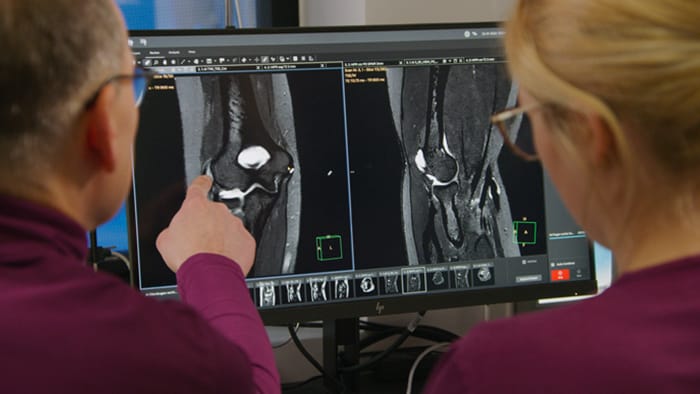

Then, because the computing capacity is so large, we have the images immediately available on the large screen. Higher resolution is very valuable. From the high-resolution 3D sequences, excellent multiplanar reconstruction can be obtained. This makes it easier and faster for us to diagnose and create reports. And while the patient is still lying in the magnet, we can already view the images and make a diagnosis. When the patient comes out, I can immediately ask whether what I see corresponds to the symptoms.”

Philips SmartSpeed is available via MR Workspace, the large-screen operator console that empowers the technologist with integrated AI protocol selection.

“The big 27-inch 4K high resolution screen makes a total difference. It shows the large planning images with much higher resolution than we were used to. Anatomic landmarks can be more easily identified, which advances the process. Now it is much easier and faster to plan the new sequences and it’s easier for us to find lesions,” says Dr. Schröter.

Powerful GPU rapidly provides images and reconstruction on large screen

Another important part of MR Workspace is the graphics processing unit (GPU), which allows on-the-fly reconstruction times for images acquired with SmartSpeed. “In addition to seeing razor-sharp images on the large 4K monitor, we also have better and faster reconstruction of the images. Using this extremely high resolution, we sometimes have sequences with up to 800 individual images. The GPU then manages to convert them in a matter of seconds into multiplanar reconstructions. Very impressive.”